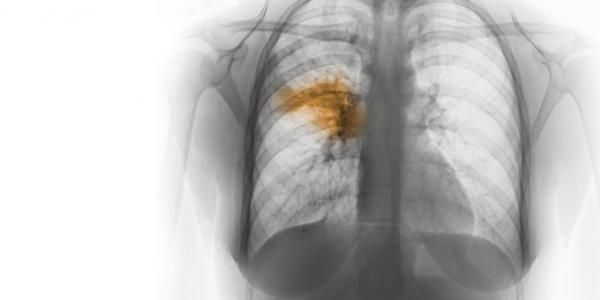

To stratify the risk factors, a score is used in ER to determine the severity of pneumonia. This is referred to as ‘CURB-65’ which stands for: C = Confusion U = Blood Urea Nitrogen > 19 mg/dl R = Respiratory rate > 30 B = Blood Pressure; systolic BP < 90 mm Hg or diastolic BP < 60 mm Hg 65 = Age > 65 Each one of the above positive finding is considered +1. Score > +3 requires in-patient care. Reference: https://www.mdcalc.com/curb-65-score-pneumonia-severity#why-use Image via: https://www.elcaminohealth.org/stay-healthy/blog/pneumonia-and-why-its-a-serious-concern